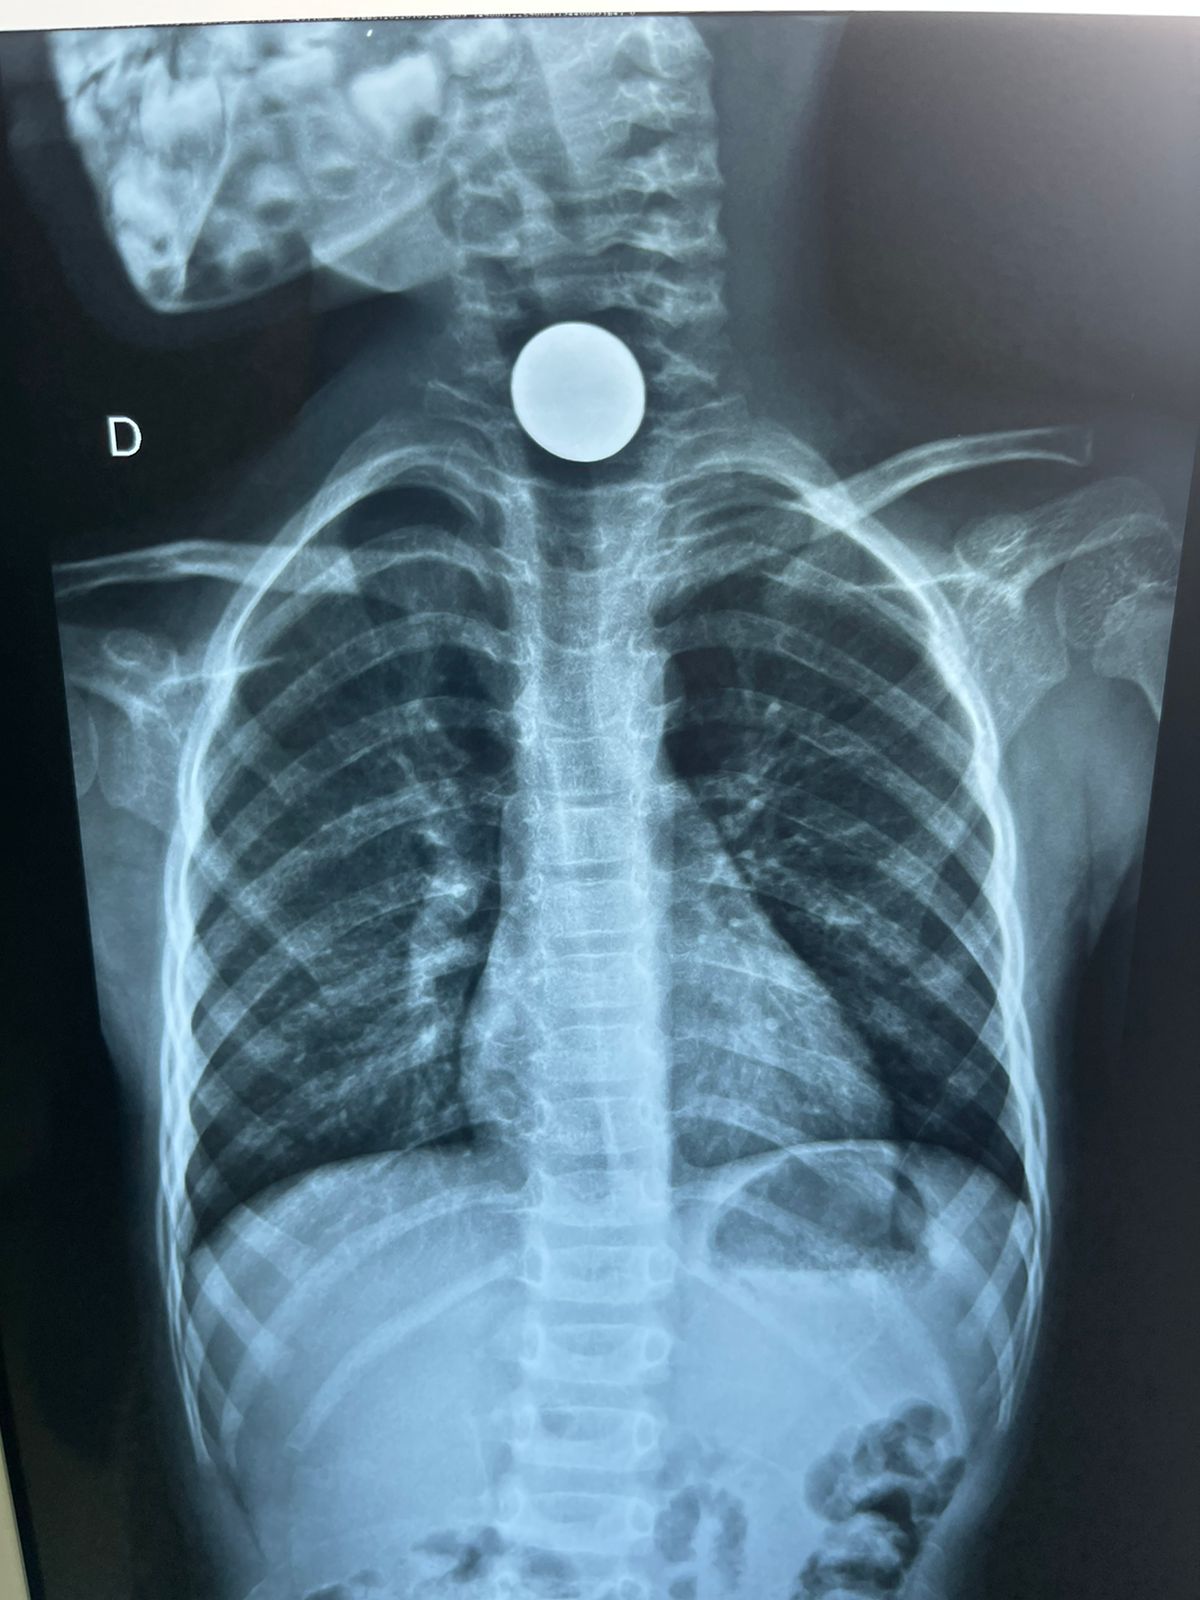

Uma criança de 5 anos de idade, moradora de Cruzeiro do Sul (AC), precisou de atendimento médico após engolir uma moeda de 10 centavos na última segunda-feira (03), o atendimento foi realizado no hospital Regional do Juruá, pelo médico Dr. Marlon Holanda.

De acordo com o médico, após a criança da entrada no hospital, foi solicitado que aguardasse o período de jejum, e foi então realizado o procedimento endoscópico com sucesso, sem precisa de realizar nenhum tipo de cirurgia. Após a retirada da moeda, a criança recebeu alta e foi encaminhada para sua residência.